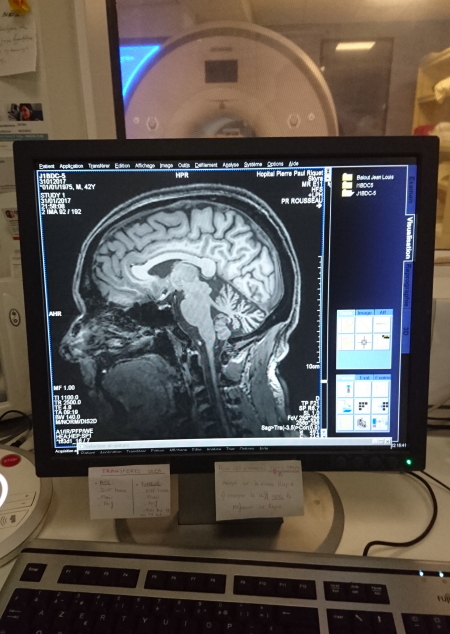

Le soir nous sommes partis à l'hopital du PURPAN en Taxi pour des IRM du cerveau.

C'est vraiment très bruyant comme machine et j'avais emmené mes boules Quies.

On m'allonge sur la table et on me cale la tête dans un casque plastique avec une belle charlotte comme couvre-chef !

Depuis la salle d'opération, l'opératrice en chef peut me parler dans un micro

l'IRM n'envoie pas d'ondes.

L'Imagerie par Résonance Magnétique consiste à réaliser des images du corps en le plaçant dans un champ magnétique.

Ainsi, les atomes d'hydrogène présents dans les tissus et dans les fluides du corps "se colorent"

Je vais donc voir mon cervau en 3D

Ce qui est significatif chez moi, c'est que je sens la découpe de la machine sur la partie ciblée et localise son mécanisme en images mentales!

Je ne peux pas expliquer ce phénomène mais c'est cool, du coup dans ce bruit incéssant qu'il y a dans ce tube, ça m'occupe et je me suis même endormi!

Couché vers minuit, et j'avais l'impression de voler et tournoyer dans mon lit suite à l'IRM ! Supers sensations.

Pour les médisant qui disent que j'ai rien dans la tête pour faire cette expérience !

Ben voilà une preuve qu'il y a un cerveau dedans!